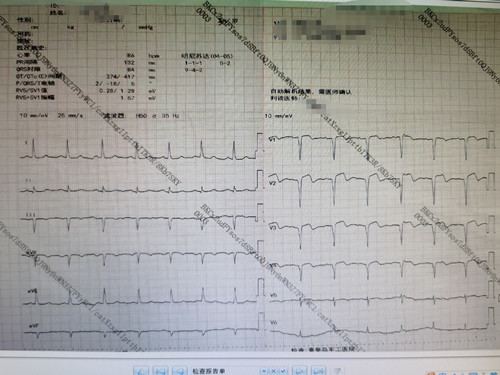

患者既往有高血压病史,每次出现胸骨后疼痛约20分钟后可逐渐缓解。王主任陷入深思:结合患者年龄、体重、病史,考虑并没有引起心梗的危险因素,而通过患者发病症状,易产生心脏神经官能症或急性胃炎导致误诊、漏诊。根据患者胸痛反复发作,导致胸痛持续不缓解,一定要仔细检查,正确判断。王主任立刻按胸痛中心诊疗流程为患者进行相关检查。果不其然,检查结果让人震惊,心电图提示:急性心肌梗死,立即住院治疗。入院后患者在第一时间得到治疗,胸痛症状逐渐缓解。